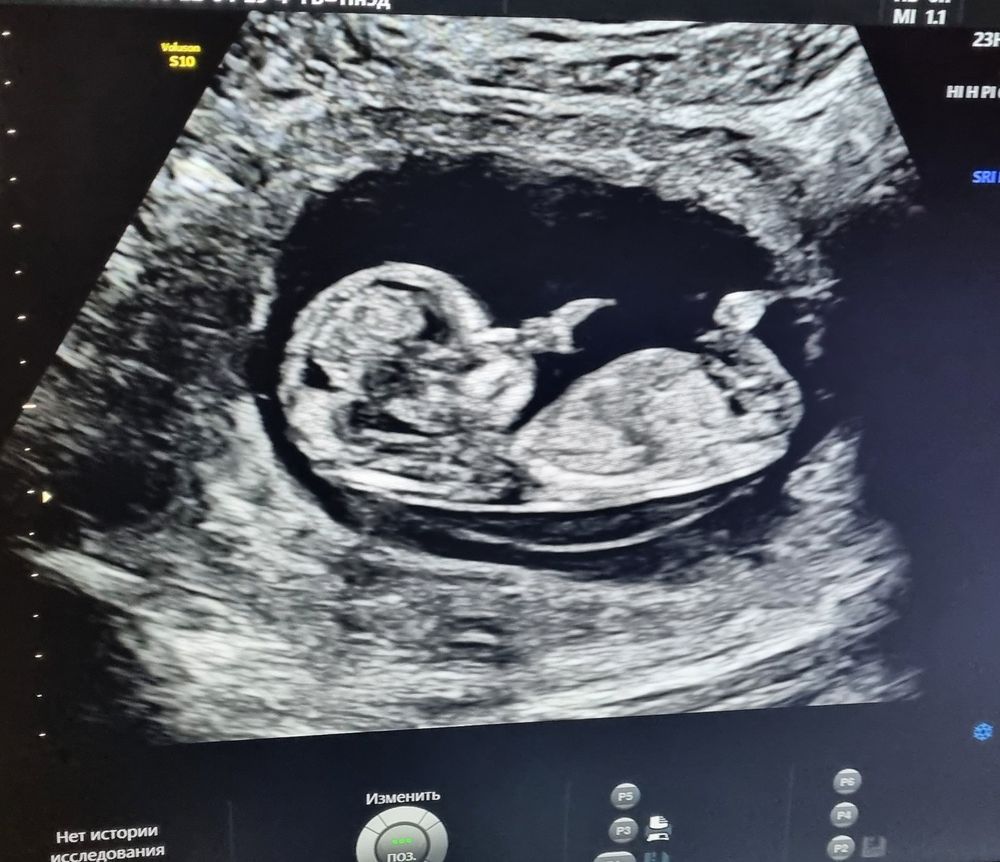

Всё о нашей беременности29.04 прошёл первый скрининг, жк отправляла в роддом, там сказали, что все хорошо по узи и срок 12 недель и 4 дня, на 5 дней больше поставили. На словах сказали, что шейно вортниковая зона в норме, носовая кость есть, размер плода 6 с чем то см. Прикрепление по задней стенке, прилижание низкое над зевом. Шейка закрыта и в норме. Малыш лежал спокойно.

30.04 поехала в платную клинику к гематологу-гинекологу, пришлось сделать ещё раз скрининг, так как от 29.04 на руки ничего не дают и толком не заполняют данные и замеры..а моему врачу нужно просмотреть все.

В платной клинике поставили срок ,как и должно быть 12 недель ровно.. и размер уже 54мм плода , как так??

Но малыш был очень активный в платном центре, на месте и секунды не мог полежать, носовую кость еле посмотрели, так как он закрывал лицо руками и вовсе отворачивался спиной постоянно.

Я не очень понимаю как может быть такая разница в размерах ?? Если даже в понедельник в другом платном центре 25го на узи он был итак 54 мм. 29го 6 см, а 30го как и в понедельник 54мм